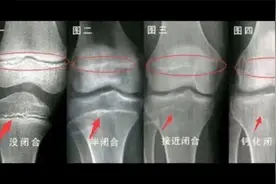

骨骺线闭合的判断